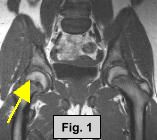

MRI FINDINGS:  The MRI was performed on AIC's high-field 1.5 Tesla short-bore Siemens Symphony.  Coronal T1 and fat suppressed turbo STIR weighted, axial proton density and T2 weighted with Fat Saturation, and sagittal DESS sequences were obtained bilaterally.  Fig. 1 (coronal T1W) shows widening and irregularity of the growth plate in the right hip.  Fig. 2 (coronal STIR) shows subtle adjacent marrow edema and moderate joint effusion.  Fig. 3 (sagittal DESS) and Fig. 4 (axial PD Fat Sat) also demonstrate the same findings.  Subtle medial displacement of the right femoral epiphysis is also noted on the coronal images.